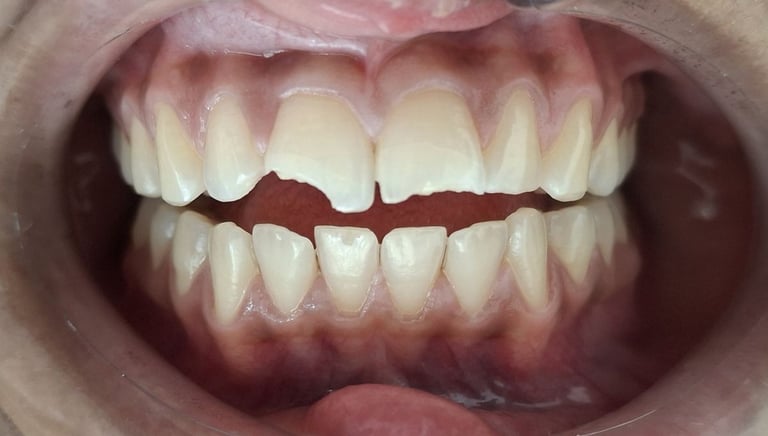

Professional Teeth Cleaning in Shyamal, Ahmedabad

Gentle, properly performed and tailored teeth cleaning for each person giving you comfort, safety and visible results. People from Shyamal and nearby areas of Ahmedabad visit our clinic for comfortable and very effective teeth cleaning.

Before

After

All images shown here are real teeth cleaning cases treated at our clinic with patient consent.

Professional teeth cleaning helps remove plaque, tarter, and surface stains that regular at home brushing can not.

At Shree Dental Care, teeth cleaning is performed gently with focus on patient experience, comfort and long term oral health.